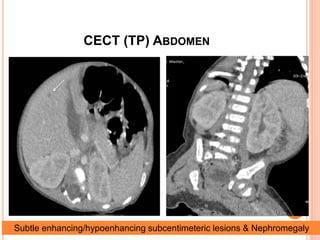

CECT (TP) ABDOMEN

Subtle enhancing/hypoenhancing subcentimeteric lesions & Nephromegaly

CT ABDOMEN

 Liver- Mildly enlarged (10-cm span), Subtle undulated

outlines.

 Few < 1 cm hypoattenuating lesions in right lobe

 No evidence of any arterial enhancing lesion

 PV 6.9-mm , HV and SP axis patent

 Spleen- Mildly enlarged (span 8.5-cm).

 Kidneys- Enlarged, Bulky, Lobulated outlines

 No free fluid